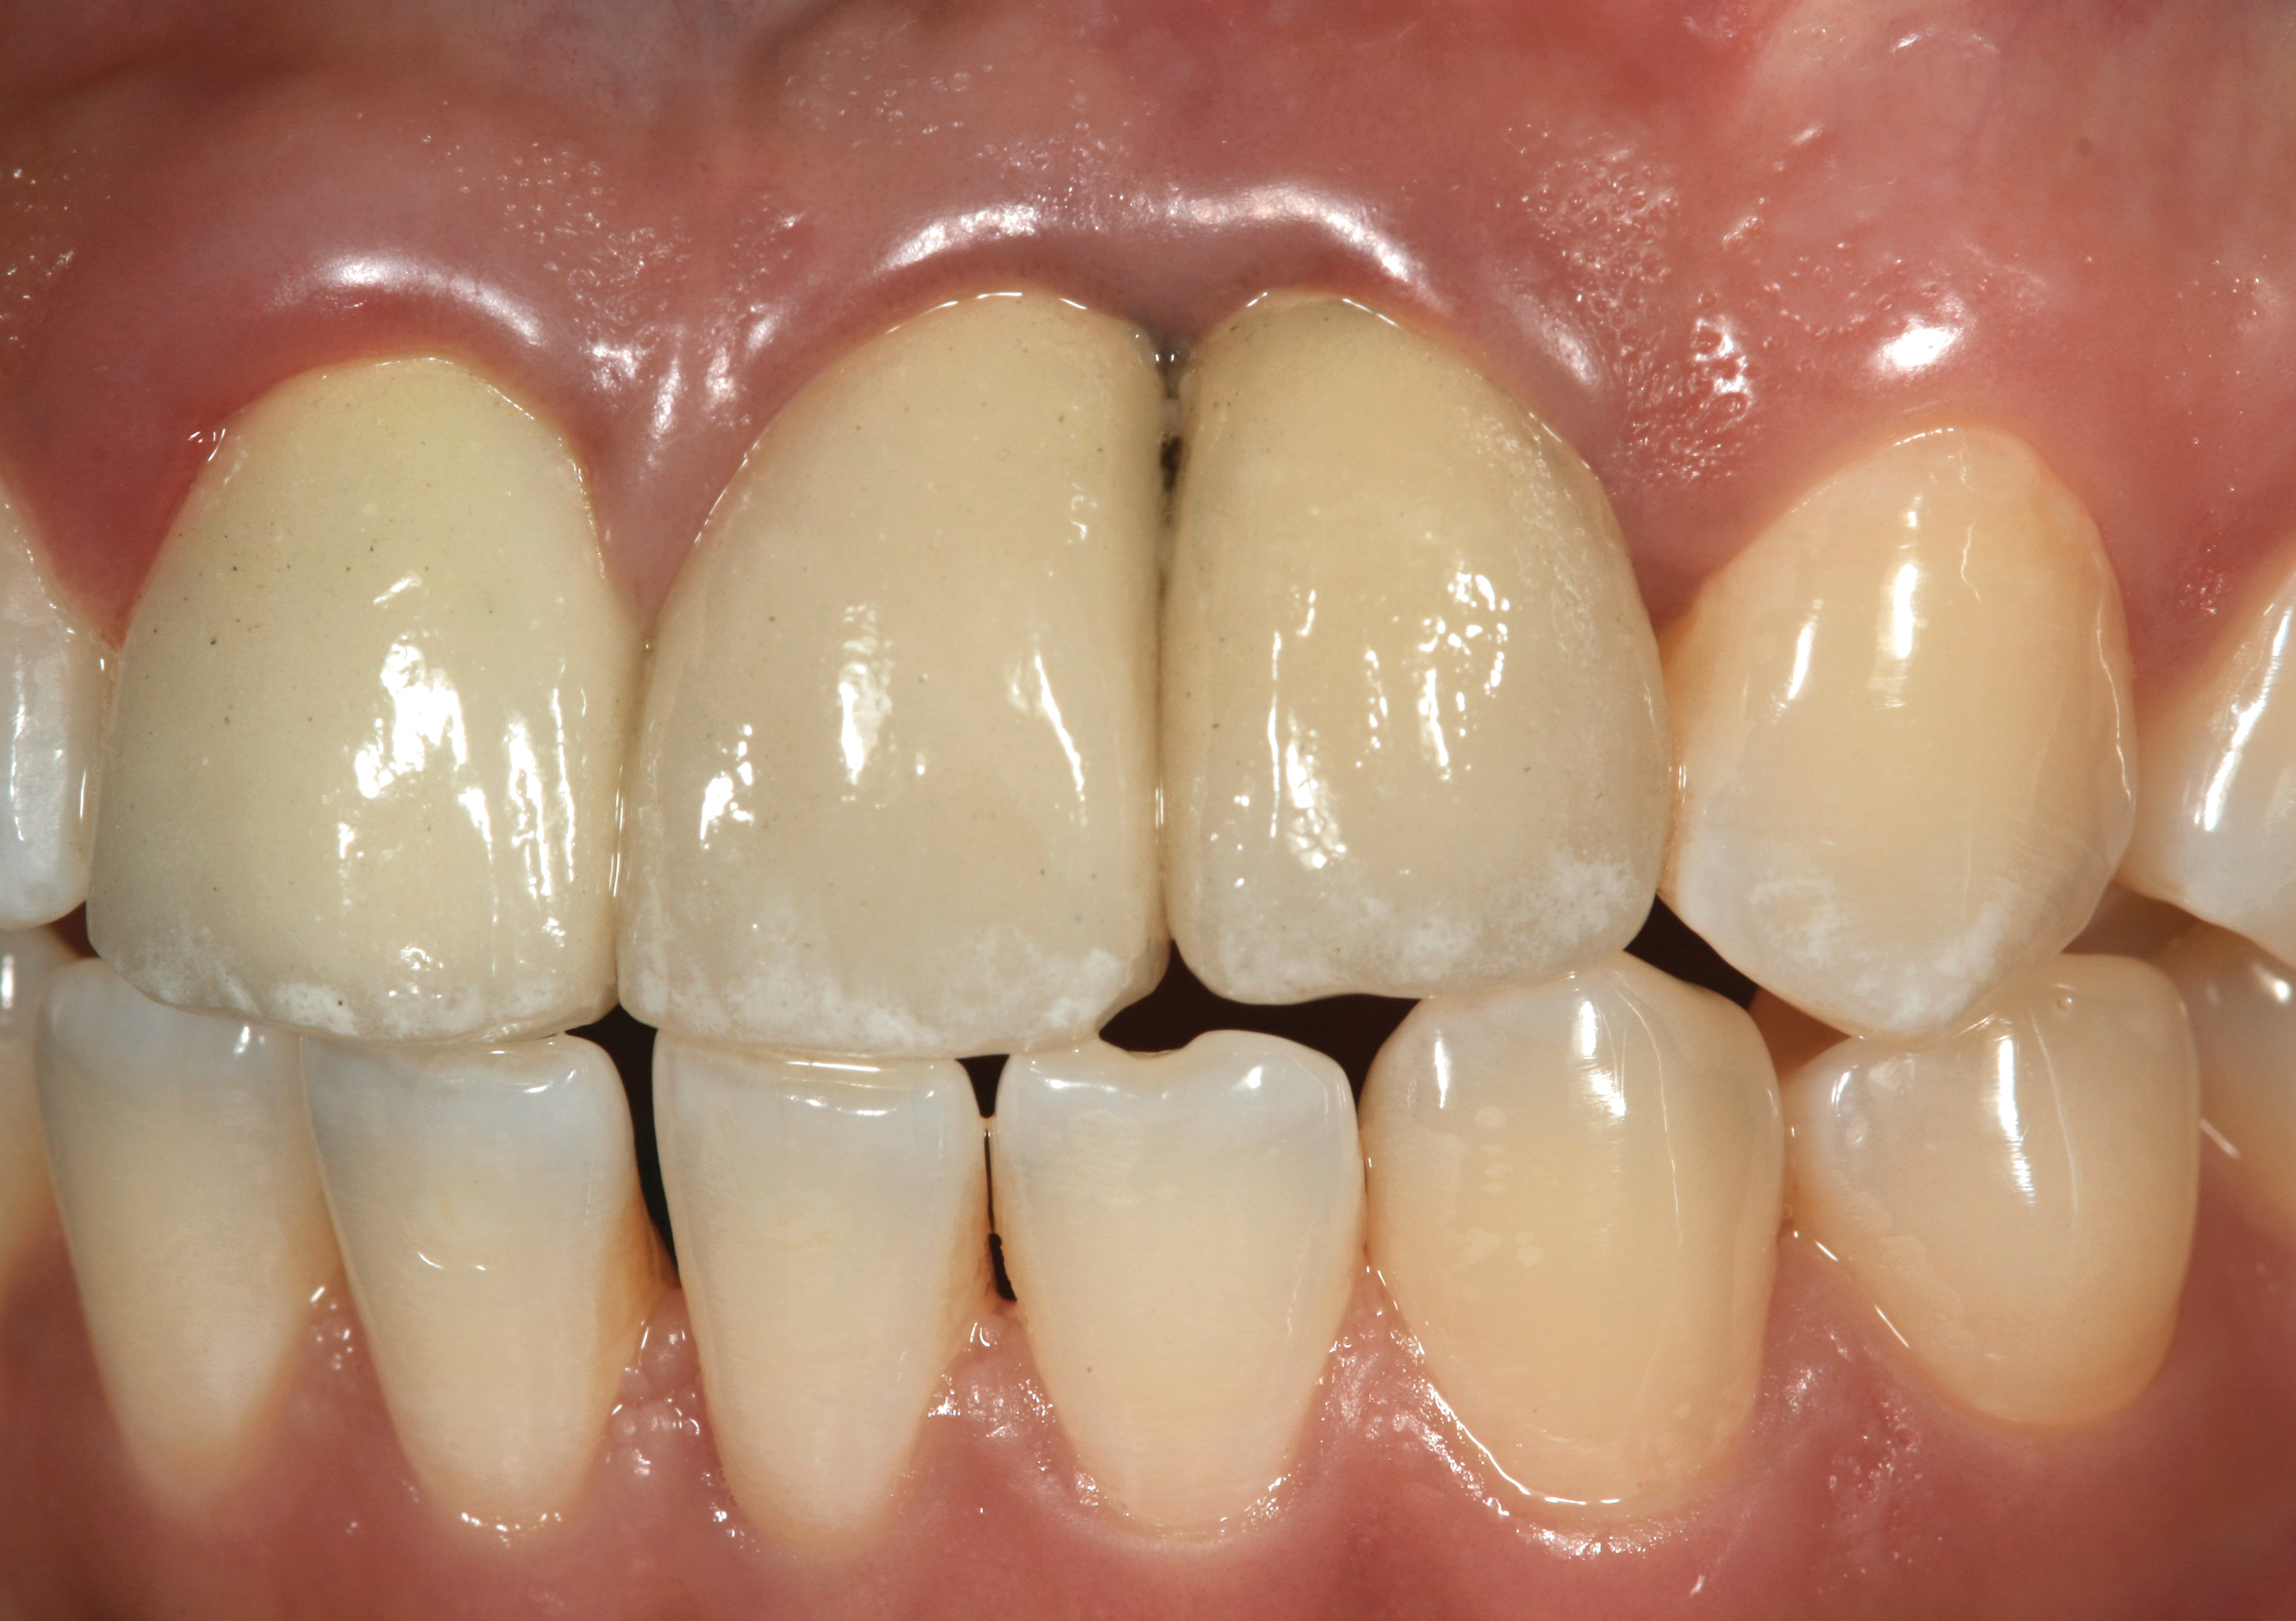

Fig 45. The definitive crown tooth No. 26 seated in place and provisionally cemented. The recession defect was eliminated with the removal and replacement of a new implant in the proper position.

Figure 45